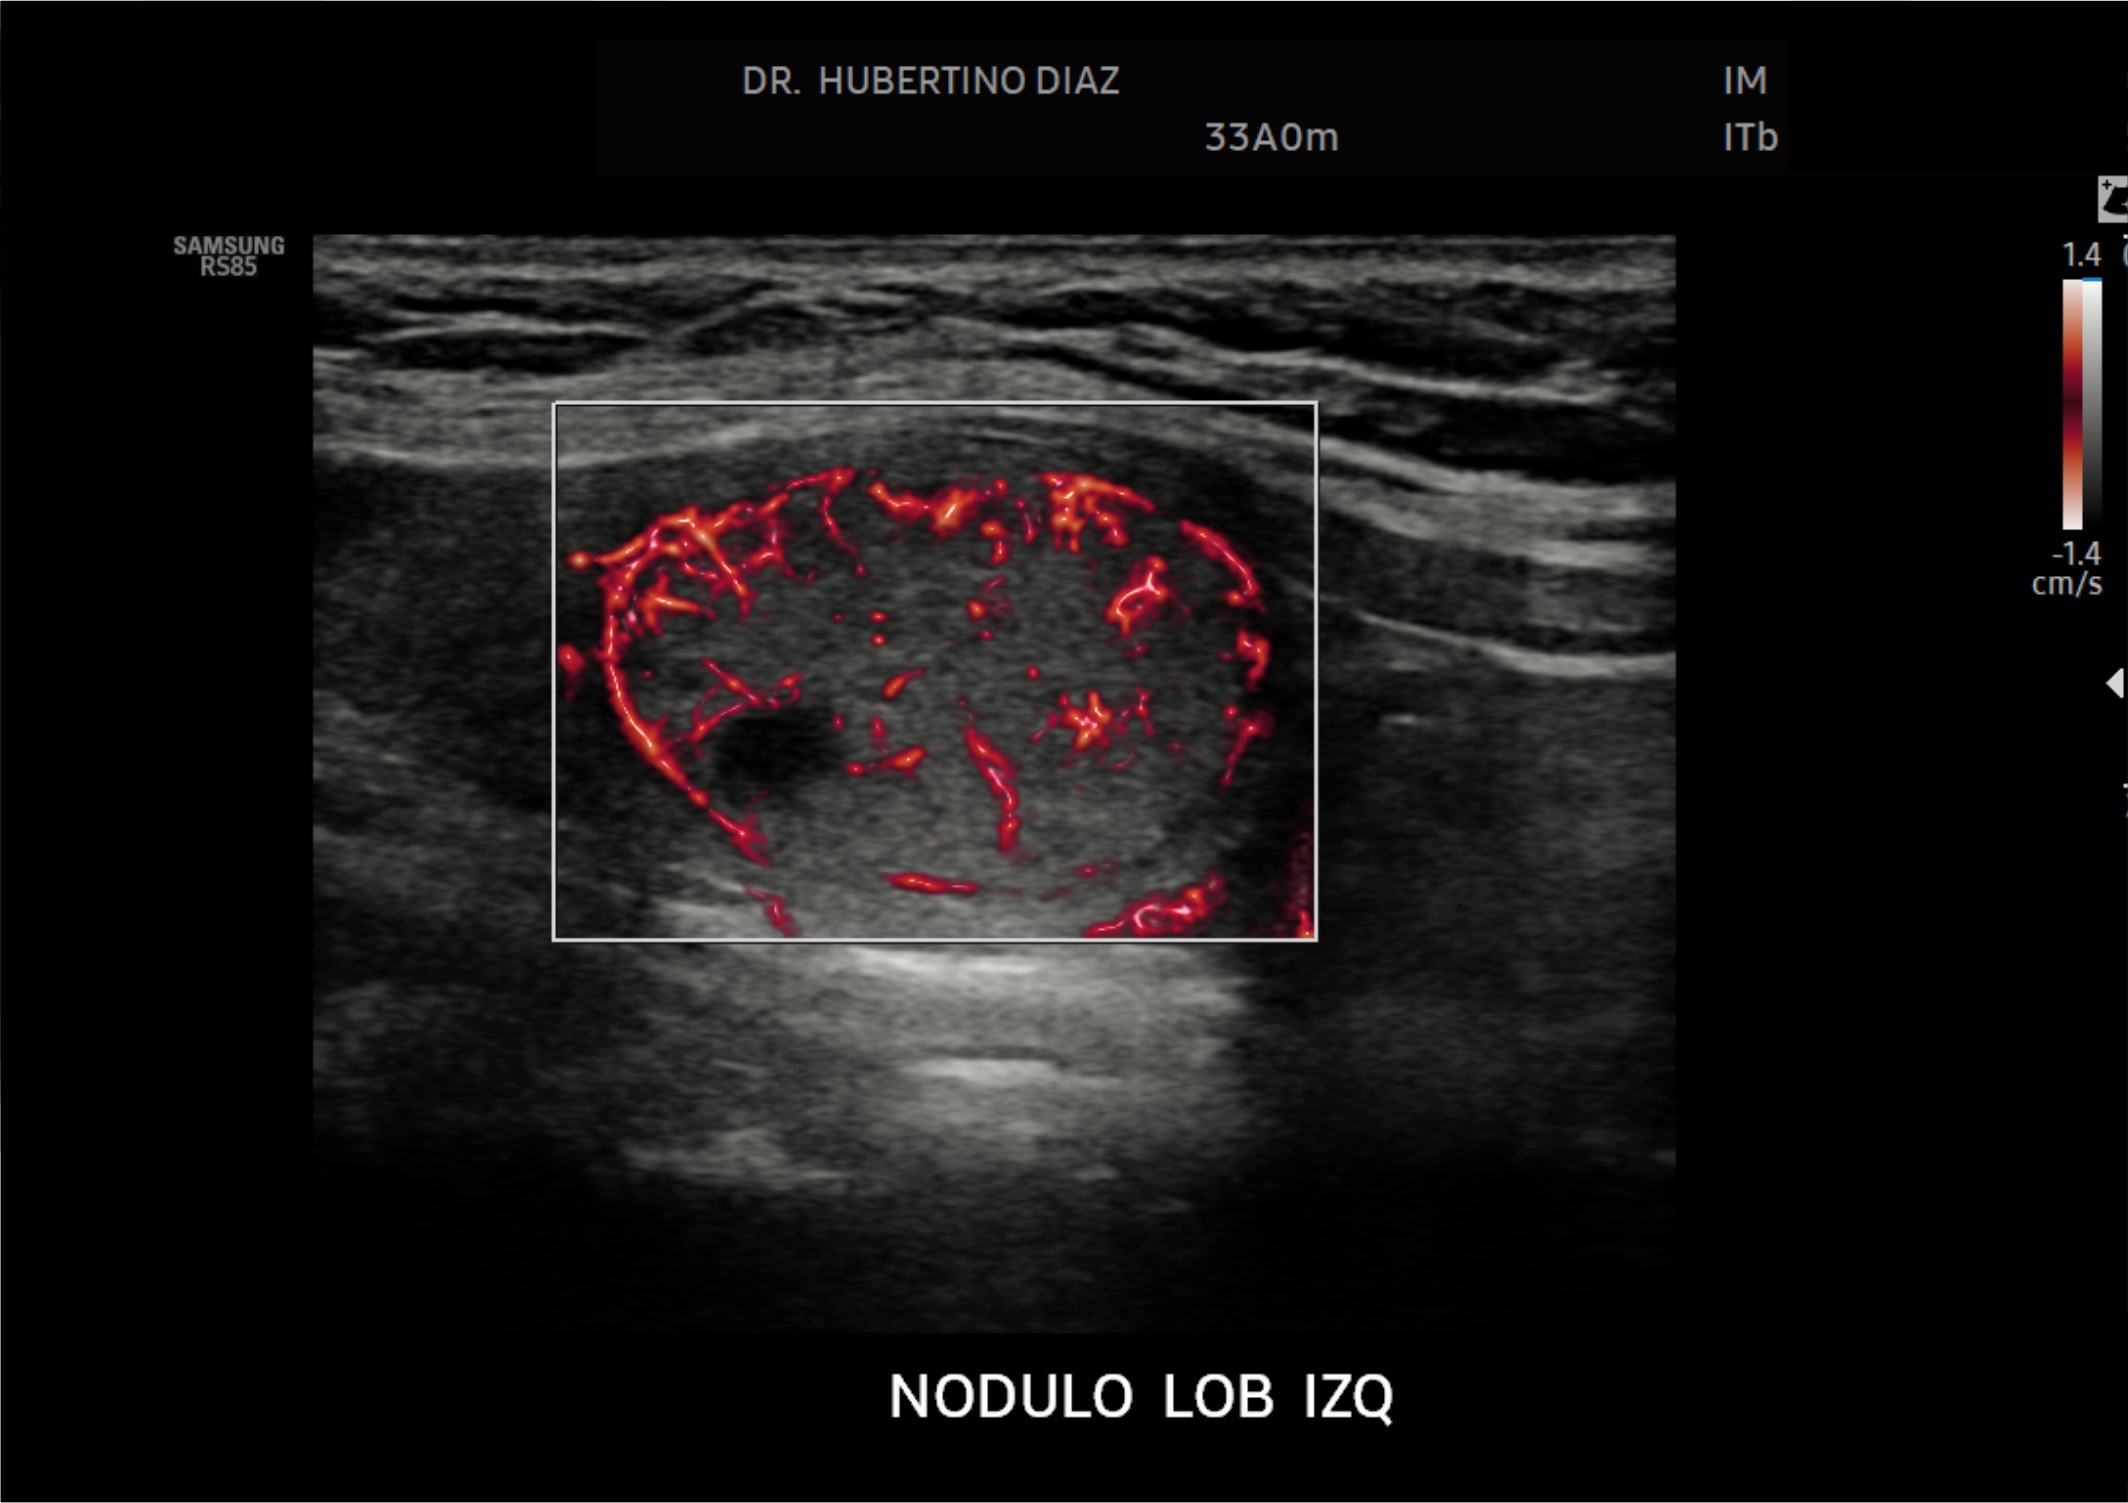

En Diagnoimagen incorporamos un enfoque de ecografía multiparamétrica, combinando modo B, Doppler color, Doppler de microflujo y elastografía, lo que nos permite una evaluación más completa y precisa en múltiples patologías.

🔹La ecografía Doppler permite evaluar el flujo sanguíneo en arterias y venas, siendo fundamental para el diagnóstico de insuficiencia venosa, várices, trombosis, estenosis carotídea y patología hepática.